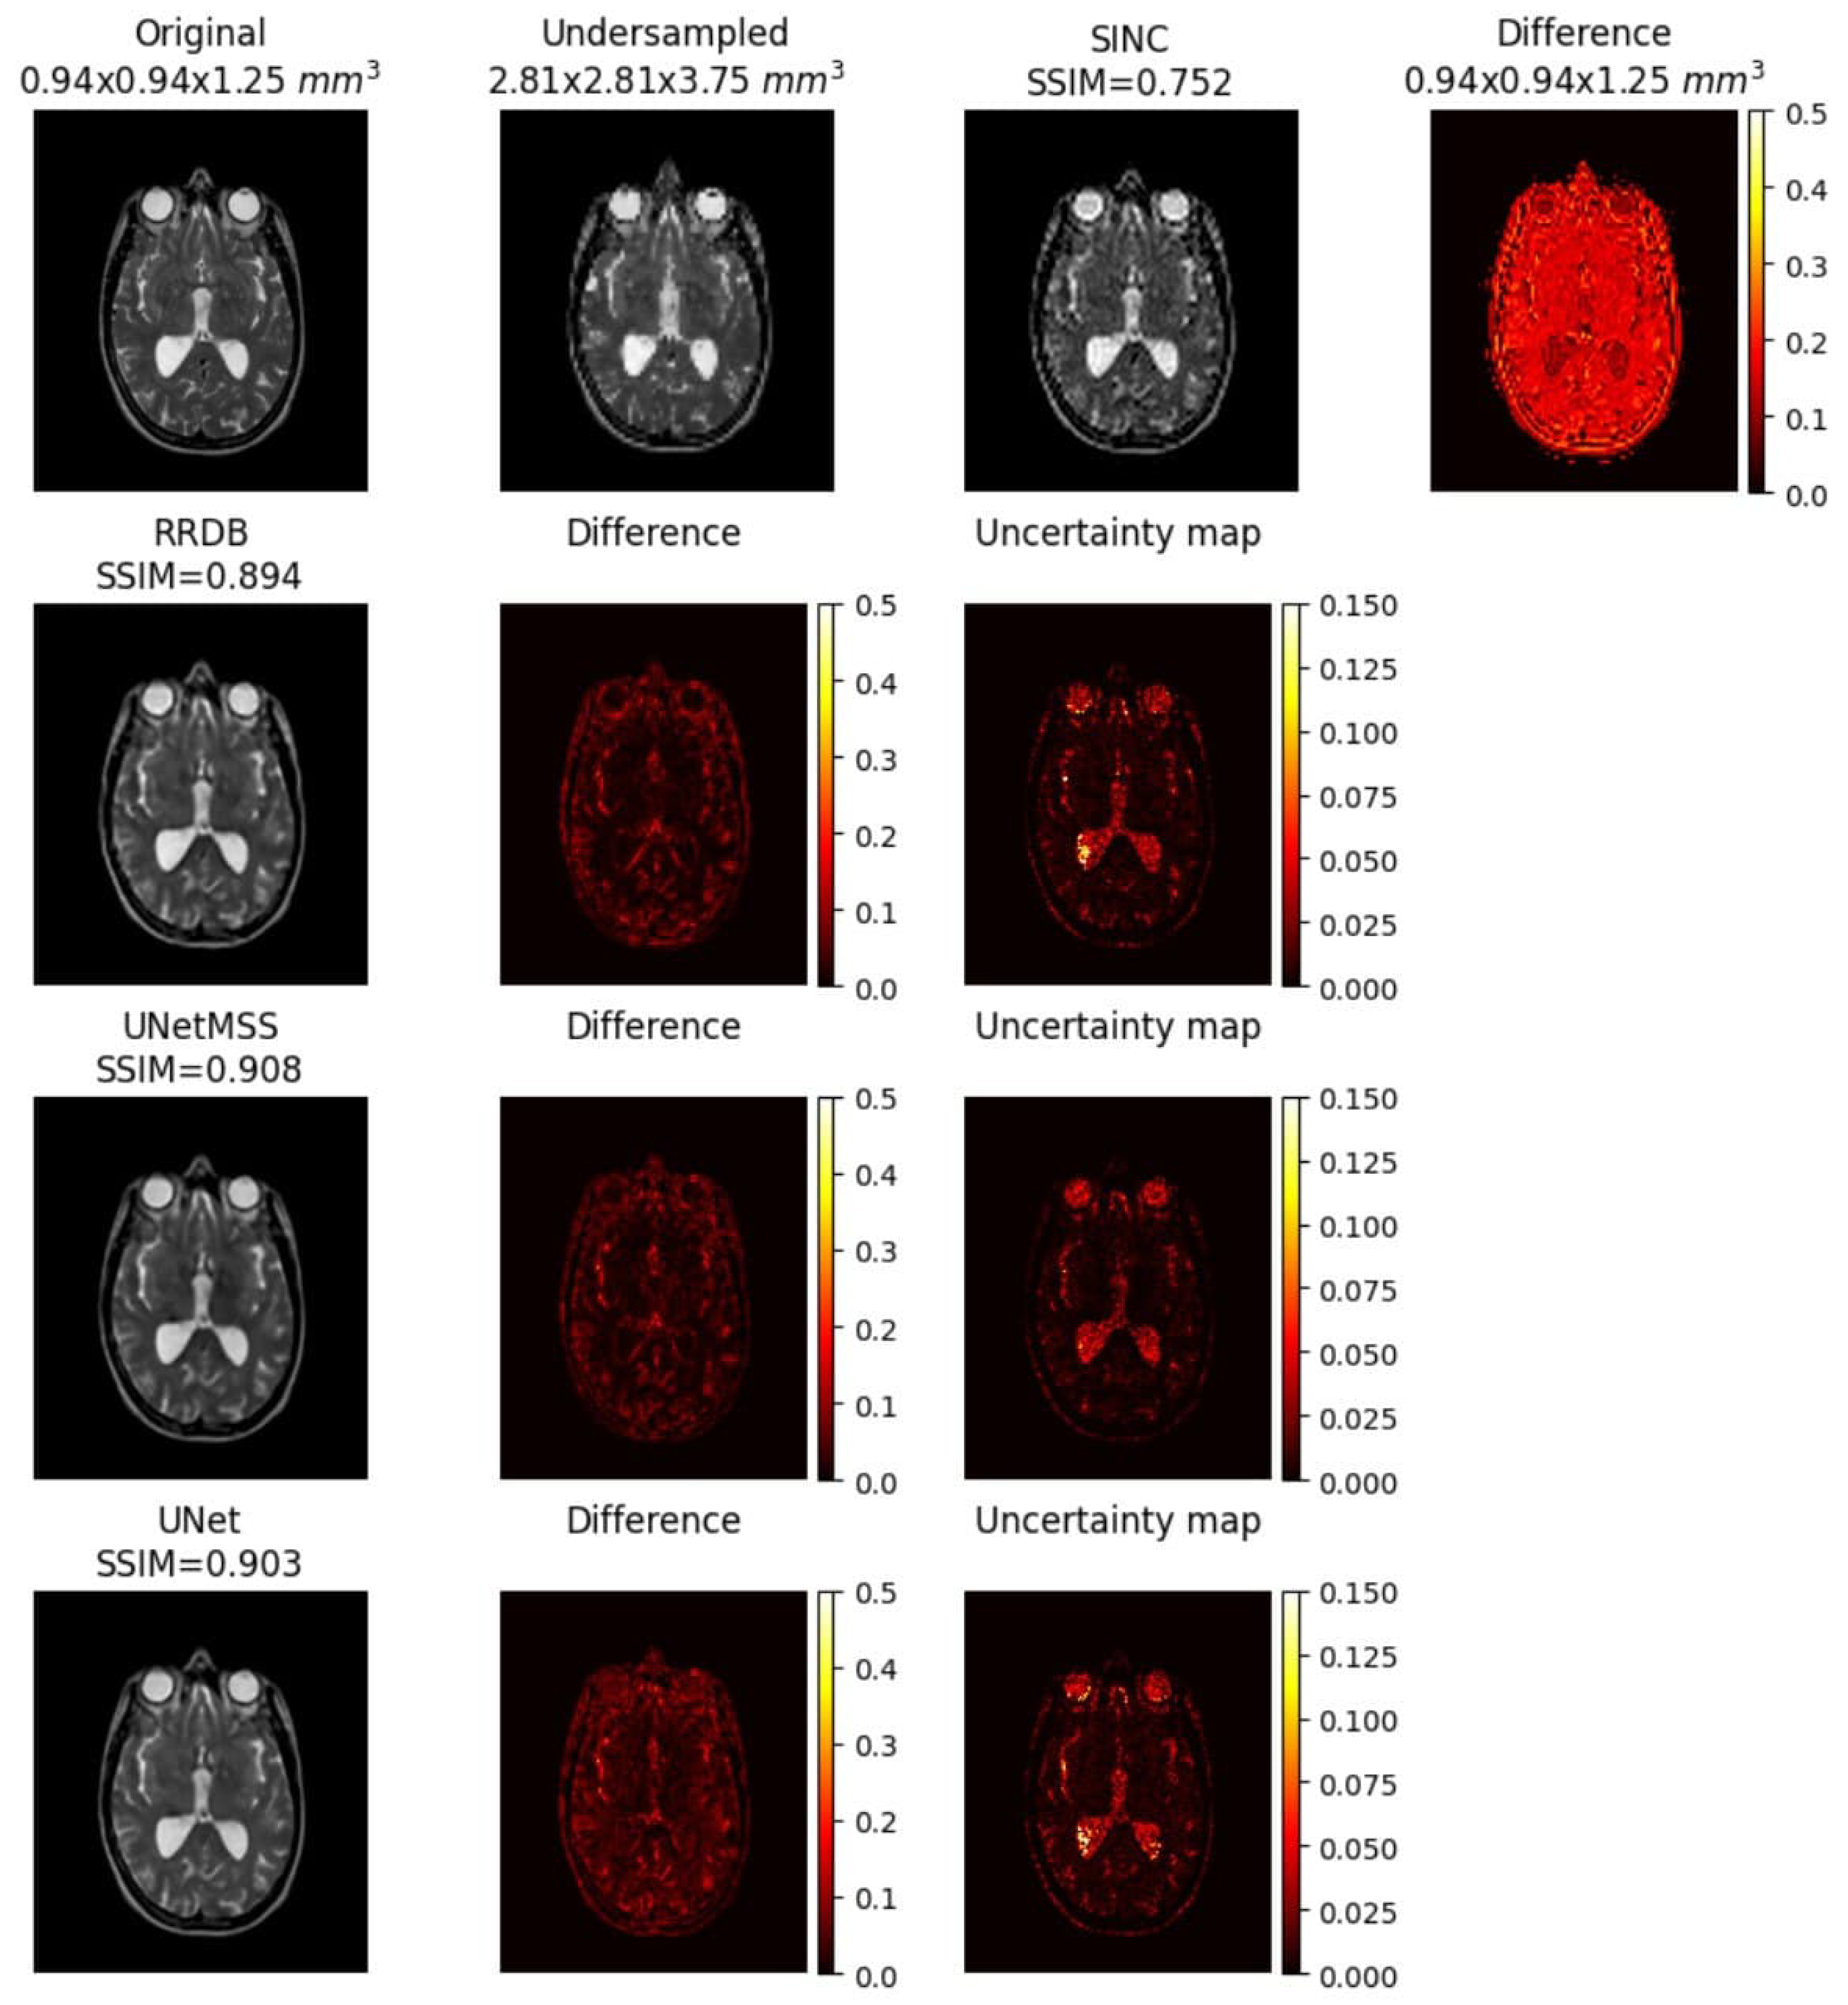

3.1.2. Main Experiments and Model Comparison

Cross Contrast Experiments

Uncertainty Mapping

- 1.

- UNet and UNetMSS perform significantly better compared to RRDB in all the acceleration factors and contasts, except and T2.

- 2.

- UNet and UNetMSS are not significantly different in all acceleration factors.